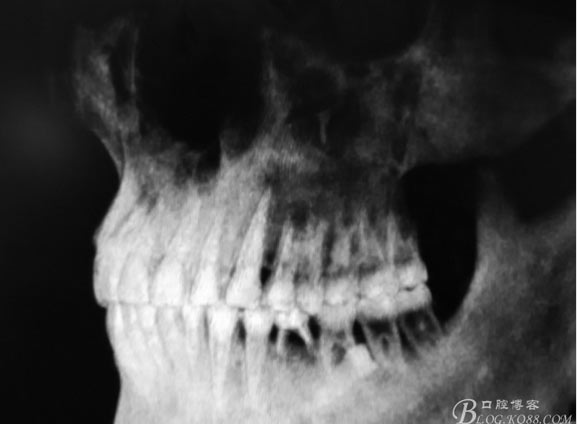

圖1.術(shù)前的全景片影像檢查,35移位至36、37之間。